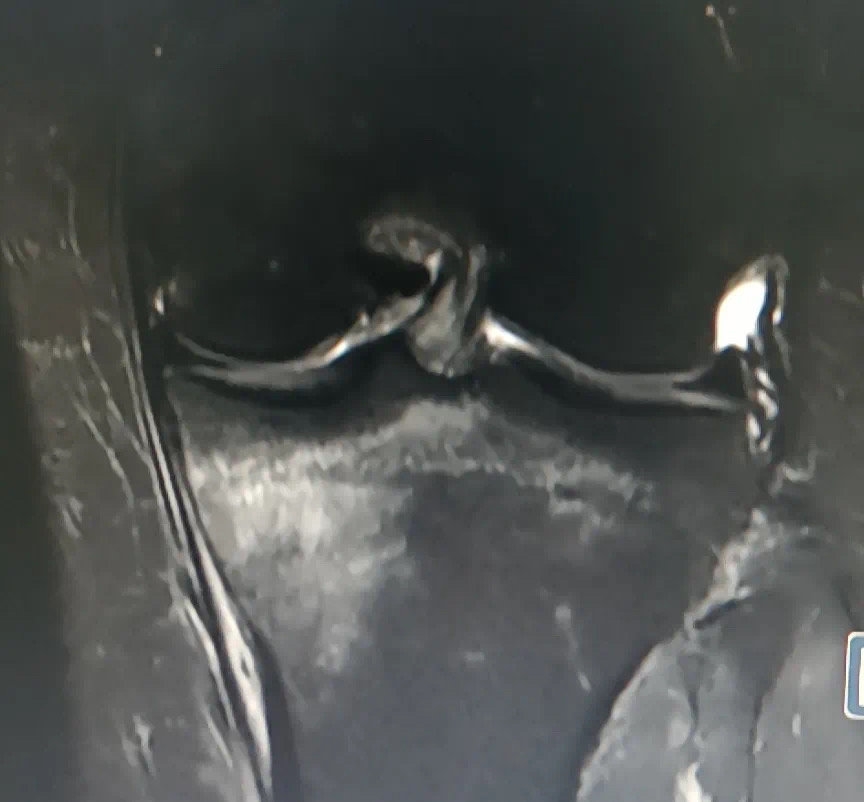

丁女士胫骨上端疲劳骨折图。医院供图

到成都市第一人民医院检查后,医生考虑丁女士为胫骨上端疲劳骨折!丁女士起初怎么都不敢相信这个结果,后面经膝关节磁共振检查明确,丁女士很困惑,不就是跳个绳吗,怎么还骨折?那怎么办呢?成都市第一人民医院骨科运动医学门诊陈志超医生建议:疲劳骨折也是一种骨折,因此一样要扶拐行走,1月内伤肢避免负重,避免进一步损伤受伤侧肢体。一个月复查一次,可以做适当物理治疗,促进骨折愈合。